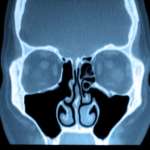

Patologia del seno mascellare, le implicazioni odontoiatriche

La patologia del seno mascellare può avere diverse origini. Un gruppo di ricercatori dell'Università di Salamanca, Spagna, ha indagato quelli di pertinenza odontoiatrica. Domandandosi...